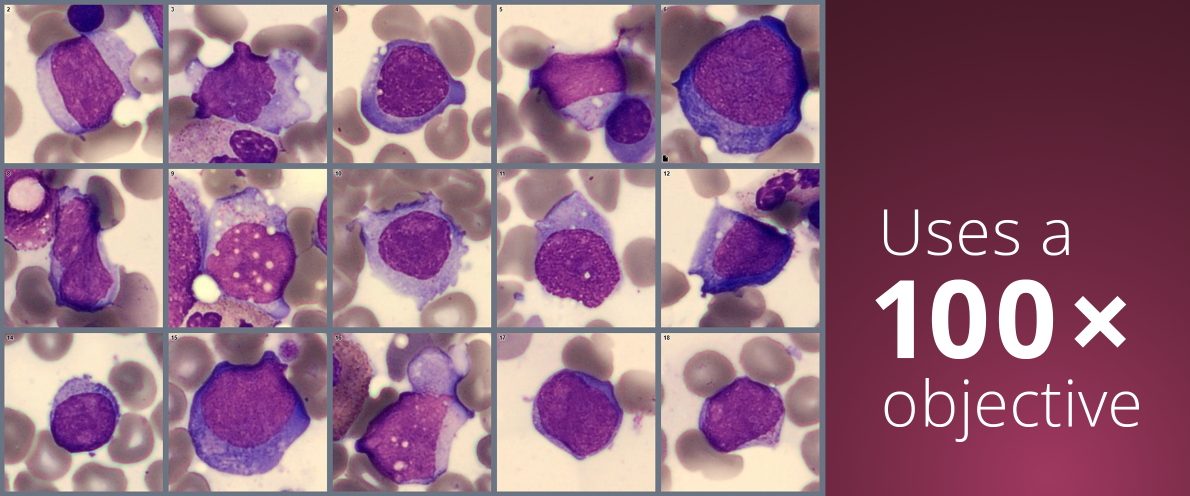

The CellaVision Bone Marrow Aspirate Application runs on the CellaVision® DC-1 analyzer using a 100× objective. Combined with BMA Review Software, it forms a bone marrow morphology solution for digital review, consultation, and verification.